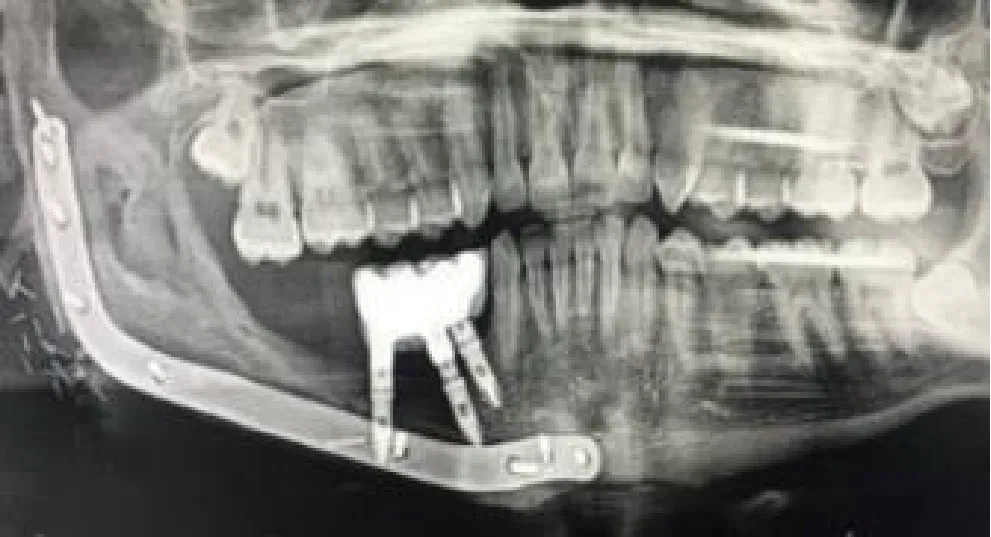

| Mandibular right body and ramus ameloblastoma | Segmental mandibulectomy | Fibula flap | sCAIS | 2 flap, 1 failed | Fixed screw retained | ![]() |

| Right mandibular body epidermoid carcinoma | Segmental mandibulectomy and neck dissection | Double-barrel fibula flap | dCAIS | 3 flap | Fixed screw retained | ![]() |

| Left mandibular body epidermoid carcinoma | Segmental mandibulectomy and Neck dissection | Iliac crest free flap | dCAIS | 2 flap | Fixed screw retained | ![]() |

| Left mandibular body ameloblastoma | Segmental mandibulectomy | Fibula flap | dCAIS | 4 flap | Fixed screw retained | ![]() |

| Right mandibular body ameloblastoma | Segmental mandibulectomy | Fibula flap | dCAIS and freehand | 3 flap | Fixed screw retained | ![]() |

| Hard palate adenoid cystic carcinoma | Central maxillectomy | Radial forearm flap | dCAIS and sCAIS | 5 Mx | Fixed screw retained | ![]() |

| Left maxilla tuberosity adenocarcinoma | IIb Brown maxillectomy | Iliac crest free flap | dCAIS and sCAIS | 3 flap | Fixed screw retained | ![]() |

| Left mandibular body epidermoid carcinoma | Segmental mandibulectomy and Neck dissection | Double-barrel fibula flap + 70 Gy | dCAIS and sCAIS | 3 flap | Fixed screw retained (Pending) | ![]() |

| Left mandibular body epidermoide carcinoma | Segmental mandibulectomy and Neck dissection | Fibula flap | dCAIS and sCAIS | 3 flap | Fixed screw retained (pending) | ![]() |

| Right hemitongue epidermoid carcinoma | Hemiglosectomy, bilateral neck dissection | Alt+ Vastus Lateralis Flap + 70 Gy | dCAIS | 6 mx | Fixed screw retained (pending) | ![]() |

| Left hemimandible ameloblastoma | Segmental mandibulectomy | Failed Fibula flap and pectoralis major | sCAIS | 5 mx | Fixed screw retained (pending) | ![]() |